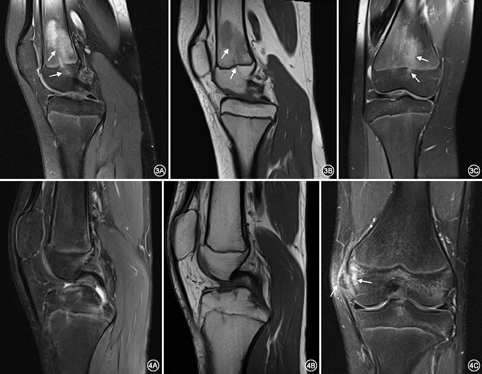

外伤组16例,共有20个水肿区域,股骨骺板区水肿14个,胫骨骺板区水肿6个。其中19个水肿区MR表现为骺板区大小不等的片状T1WI低信号,PD-FS高信号,以PD-FS显示最佳(图3),仅1例患者骺板区水肿表现为线状T1WI低信号,PD-FS高信号。此外,4例患者MR显示骺板局部不规则变薄,PD-FS序列局部信号增高。水肿范围(26.2±8.8)mm,其中水肿区域的范围10.3~17.5 mm有2个,17.5~35.0 mm有15个,35.0~42.7 mm有3个。此外,16例外伤患者中,5例患者仅表现为片状骺板区水肿,范围较大,但有明确的外伤史。5例患者有明显的骨折征象,并经手术证实(图4)。5例骨骺板损伤。4例手术证实为半月板损伤。内侧副韧带损伤及交叉韧带各2例(表2)。

12例无外伤患者共有15个水肿区,9个位于股骨远端(图1),4个位于胫骨近端(图2),2个位于腓骨近端。MR表现为以骺板为中心的局限性线状或小斑片状T1WI低信号,PD-FS高信号区,病变波及邻近的骨骺和干骺端,而骨骺板未见异常。其中2个水肿区表现为骺板边缘线状水肿区,其余水肿区均为不同程度斑片状水肿。水肿范围(14.5±6.6)mm,其中水肿区域的范围3.9~7.9 mm的有3个,7.9~21.1 mm有10个,21.1~28.8 mm有2个(表1)。本组MR检查均未发现可以解释膝关节疼痛的异常征象,所有病例均经随访证实患者未进行任何治疗,膝关节疼痛逐渐减轻,最终疼痛完全消失,骺板区水肿范围缩小或消失。